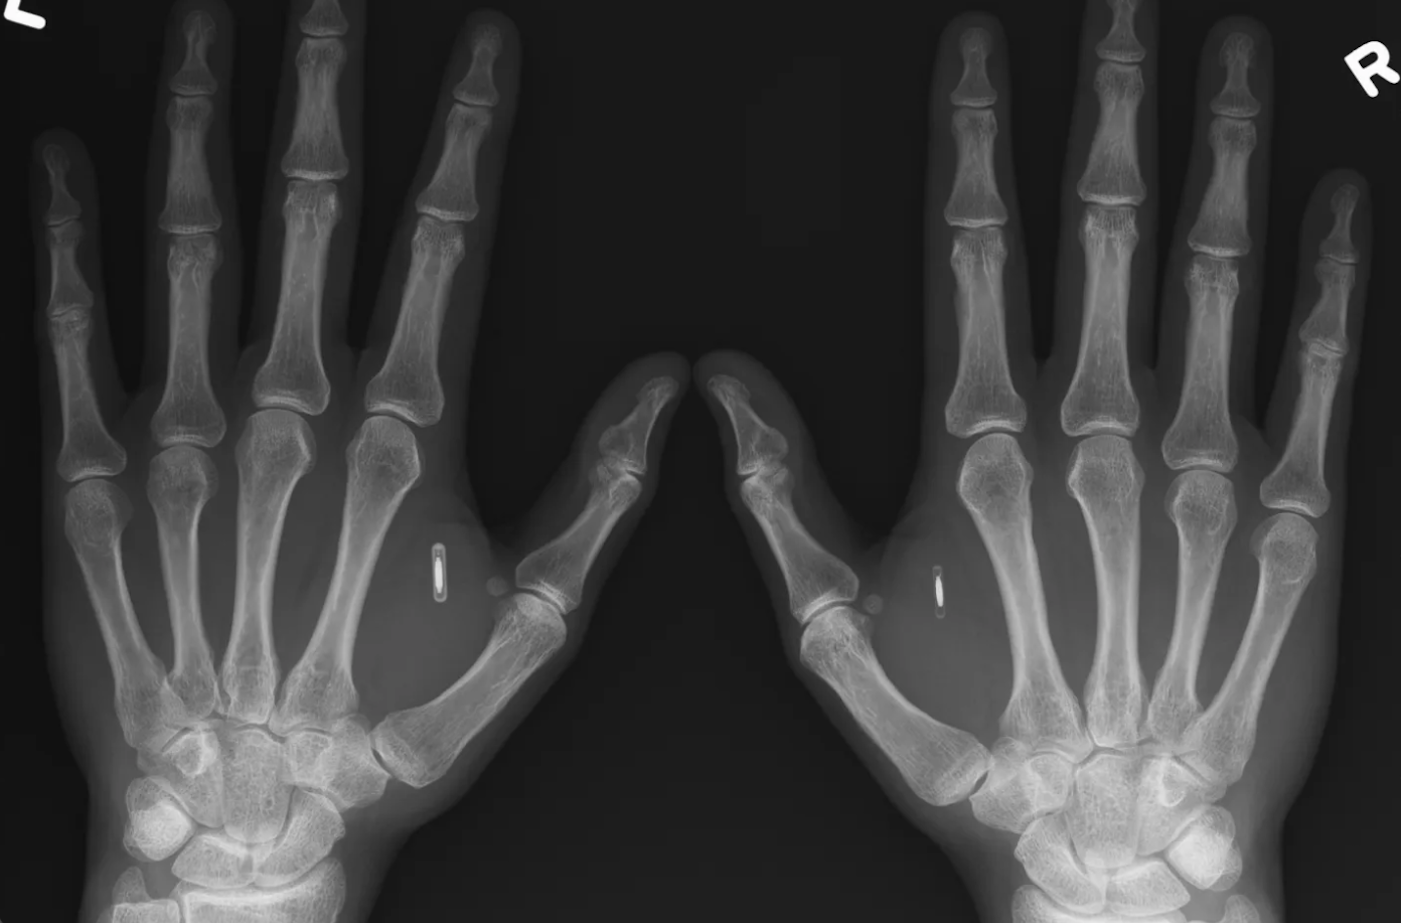

When Donna Haraway describes the cyborg, she is not predicting a chrome-plated robot future. She is pointing out something more unsettling and more empowering: the human body has never been sealed off from technology. We are hybrid beings already. The question is whether that hybridity expands our freedom or narrows it. One contemporary example where hybridity is playing out as liberation is the rise of biohacking and wearable self-tracking culture. From NFC chips implanted in hands to smart rings that monitor sleep and heart rate, people are voluntarily merging with technology in order to extend their capabilities. This is not science fiction. It is happening in gyms, tech communities, medical labs, and even everyday households.

Individuals implant NFC chips to unlock doors with their hands. Others use subdermal magnets to sense electromagnetic fields. Wearables provide insight into sleep cycles, stress patterns, and metabolic responses. What’s significant here is not the gadget, it’s the mindset. The body is treated as adaptable, upgradeable, open to redesign. That perspective challenges the idea that the “natural body” is fixed or complete. Janelle Monáe’s android persona in The ArchAndroid reimagines technological embodiment not as loss of humanity but as expanded identity. In real life, biohackers often describe implants and devices as ways of becoming “more fully themselves,” not less. Technology becomes a creative medium for the self.